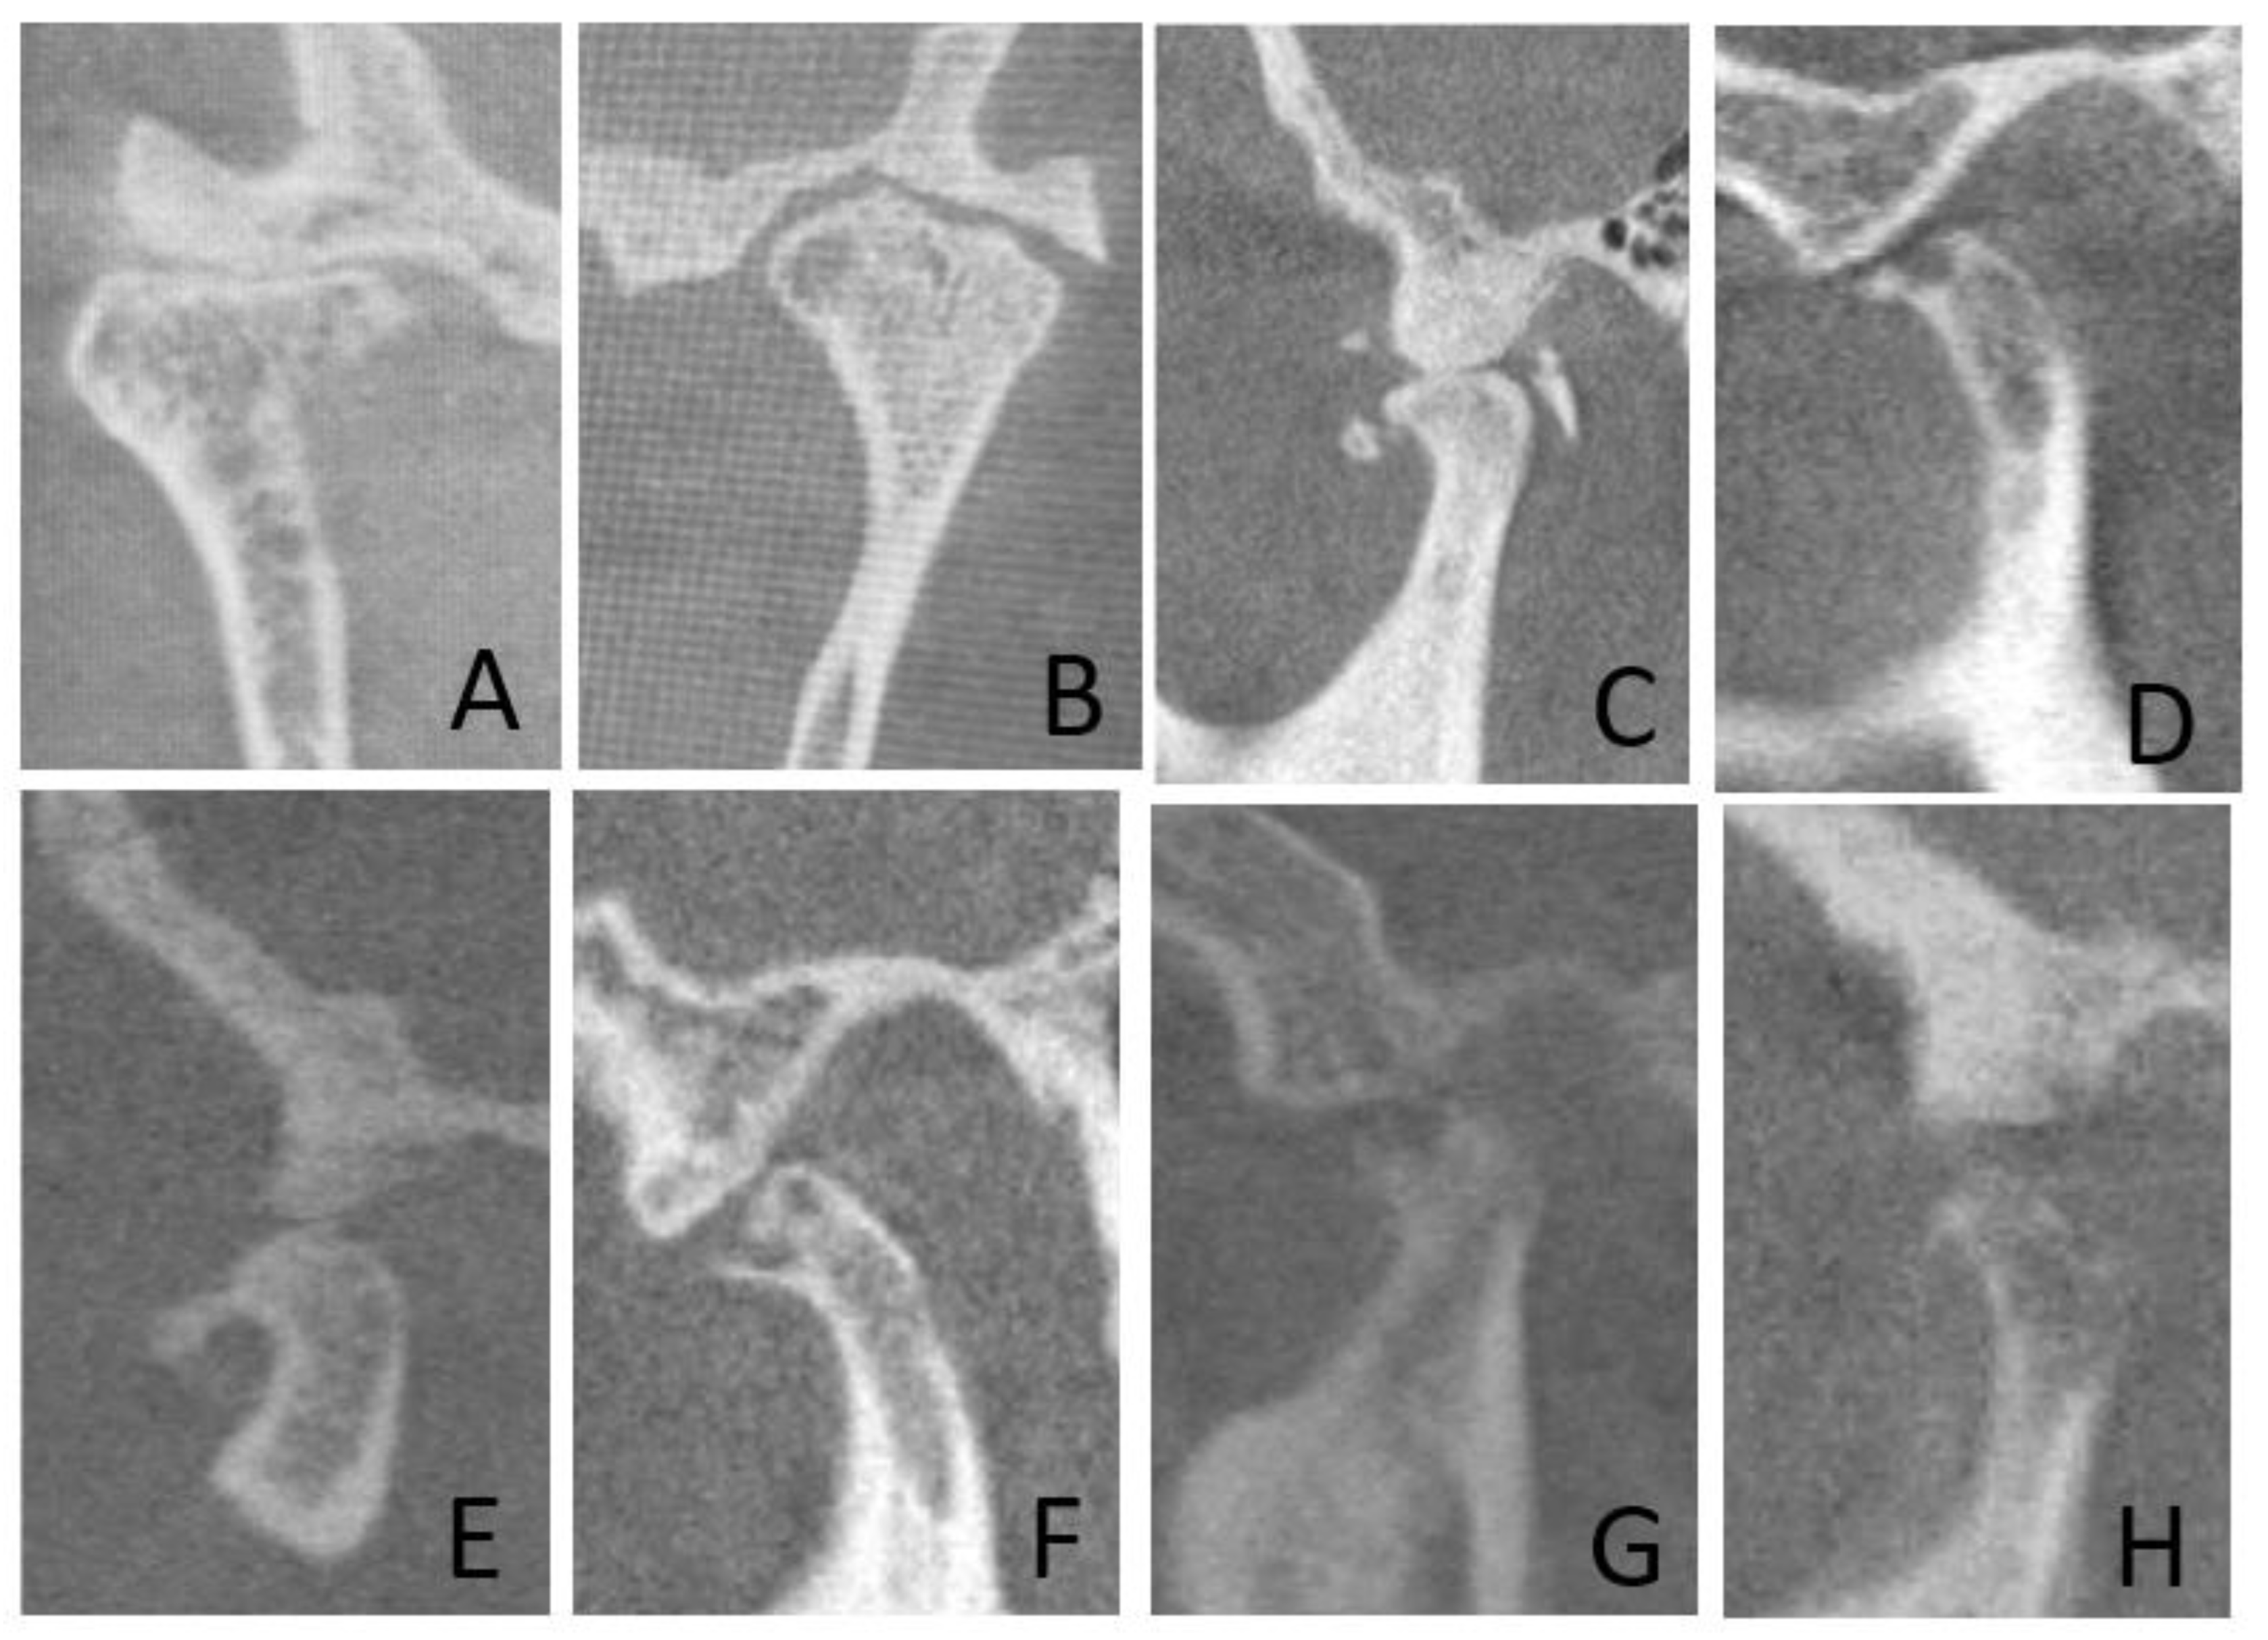

| Condylar erosion-1 | 69 (53.1%) | 41 (31.5%) | 110 (42.3%) | <0.001 | 0.97 | <0.001 |

| Condylar erosion-2 | 69 (53.1%) | 38 (29.2%) | 107 (41.2%) | <0.001 | ||

| Condylar flattening-1 | 49 (37.7%) | 24 (18.5%) | 73 (28.1%) | 0.001 | 0.98 | <0.001 |

| Condylar flattening-2 | 48 (36.9%) | 23 (17.7%) | 71 (27.3%) | 0.001 | ||

| Subcortical sclerosis-1 | 54 (41.5%) | 17 (13.1%) | 71 (27.3%) | <0.001 | 0.99 | <0.001 |

| Subcortical sclerosis-2 | 54 (41.5%) | 18 (13.8%) | 72 (27.7%) | <0.001 | ||

| Osteophyte-1 | 50 (38.5%) | 22 (16.9%) | 72 (27.7%) | <0.001 | 0.99 | <0.001 |

| Osteophyte-2 | 50 (38.5%) | 21 (16.2%) | 71 (27.3%) | <0.001 | ||

| Subcortical cyst-1 | 44 (33.8%) | 17 (13.1%) | 61 (23.5%) | <0.001 | 1 | <0.001 |

| Subcortical cyst-2 | 44 (33.8%) | 17 (13.1%) | 61 (23.5%) | <0.001 | ||

| Bifid condyle-1 | 3 (2.3%) | 9 (6.9%) | 12 (4.6%) | 0.139 | 1 | <0.001 |

| Bifid condyle-2 | 3 (2.3%) | 9 (6.9%) | 12 (4.6%) | 0.139 | ||

| Articular eminence resorption-1 | 21 (16.2%) | 4 (3.1%) | 25 (9.6%) | 0.001 | 1 | <0.001 |

| Articular eminence resorption-2 | 21 (16.2%) | 4 (3.1%) | 25 (9.6%) | 0.001 | ||

| Articular eminence flattening-1 | 10 (7.7%) | 1 (0.8%) | 11 (4.2%) | 0.014 | 0.95 | <0.001 |

| Articular eminence flattening-2 | 11 (8.5%) | 1 (0.8%) | 12 (4.6%) | 0.008 | ||

| Loose joint bodies-1 | 6 (4.6%) | 2 (1.5%) | 8 (3.1%) | 0.281 | 1 | <0.001 |

| Loose joint bodies-2 | 6 (4.6%) | 2 (1.5%) | 8 (3.1%) | 0.281 | ||

| Ankylosis-1 | 5 (3.8%) | 3 (2.3%) | 8 (3.1%) | 0.722 | 1 | <0.001 |

| Ankylosis-2 | 5 (3.8%) | 3 (2.3%) | 8 (3.1%) | 0.722 | ||

| Joint space narrowing-1 | 25 (19.2%) | 15 (11.5%) | 40 (15.4%) | 0.122 | 0.98 | <0.001 |

| Joint space narrowing-2 | 25 (19.2%) | 14 (10.8%) | 39 (15%) | 0.082 | ||

| Increased joint space-1 | 0 (0%) | 1 (0.8%) | 1 (0.4%) | 0.999 | 1 | <0.001 |

| Increased joint space-2 | 0 (0%) | 1 (0.8%) | 1 (0.4%) | 0.999 |